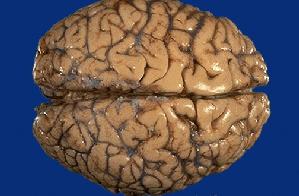

Often times families have questions concerning what Alzheimer's does to the actual brain.

The following photographs will show you.

(These are actual photos of a normal brain and one affected by AD. I'm sorry they are so explicit, but I felt they were important to include.)

Normal Brain